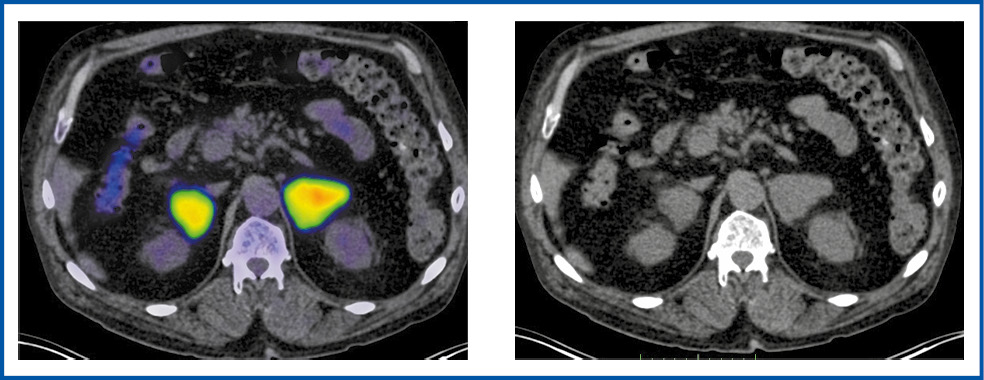

Согласно полученным данным диапазон колебаний его уровня составил 3,54–22,29, медиана – 10,0. Значение SUVmax≥10 наблюдали у 5 (55,6%) пациентов, а медиана в данной группе составляла 13,9. Максимальная величина SUVmax отмечена при двухсторонней локализации образований, достигая 22,29 (рис. 4), а минимальный его показатель – 3,54.

Рис. 4. Больной А., 65 лет. В аксиальной проекции ПЭТ/КТ- и КТ-исследовании определяются объемные образования в надпочечниках с обеих сторон размерами слева до 41×51 мм, справа – до 38×28 мм, с гиперфиксацией 18F-ФДГ, SUVmax – 22,29.

Fig. 4. Patient A., 65 years old. Axial view of PET/CT and CT imaging: there are mass lesions in the adrenal glands on both sides, up to 41×51 mm on the left and up to 38×28 mm on the right, with 18F-FDG hyper uptake; SUVmax is 22.29.